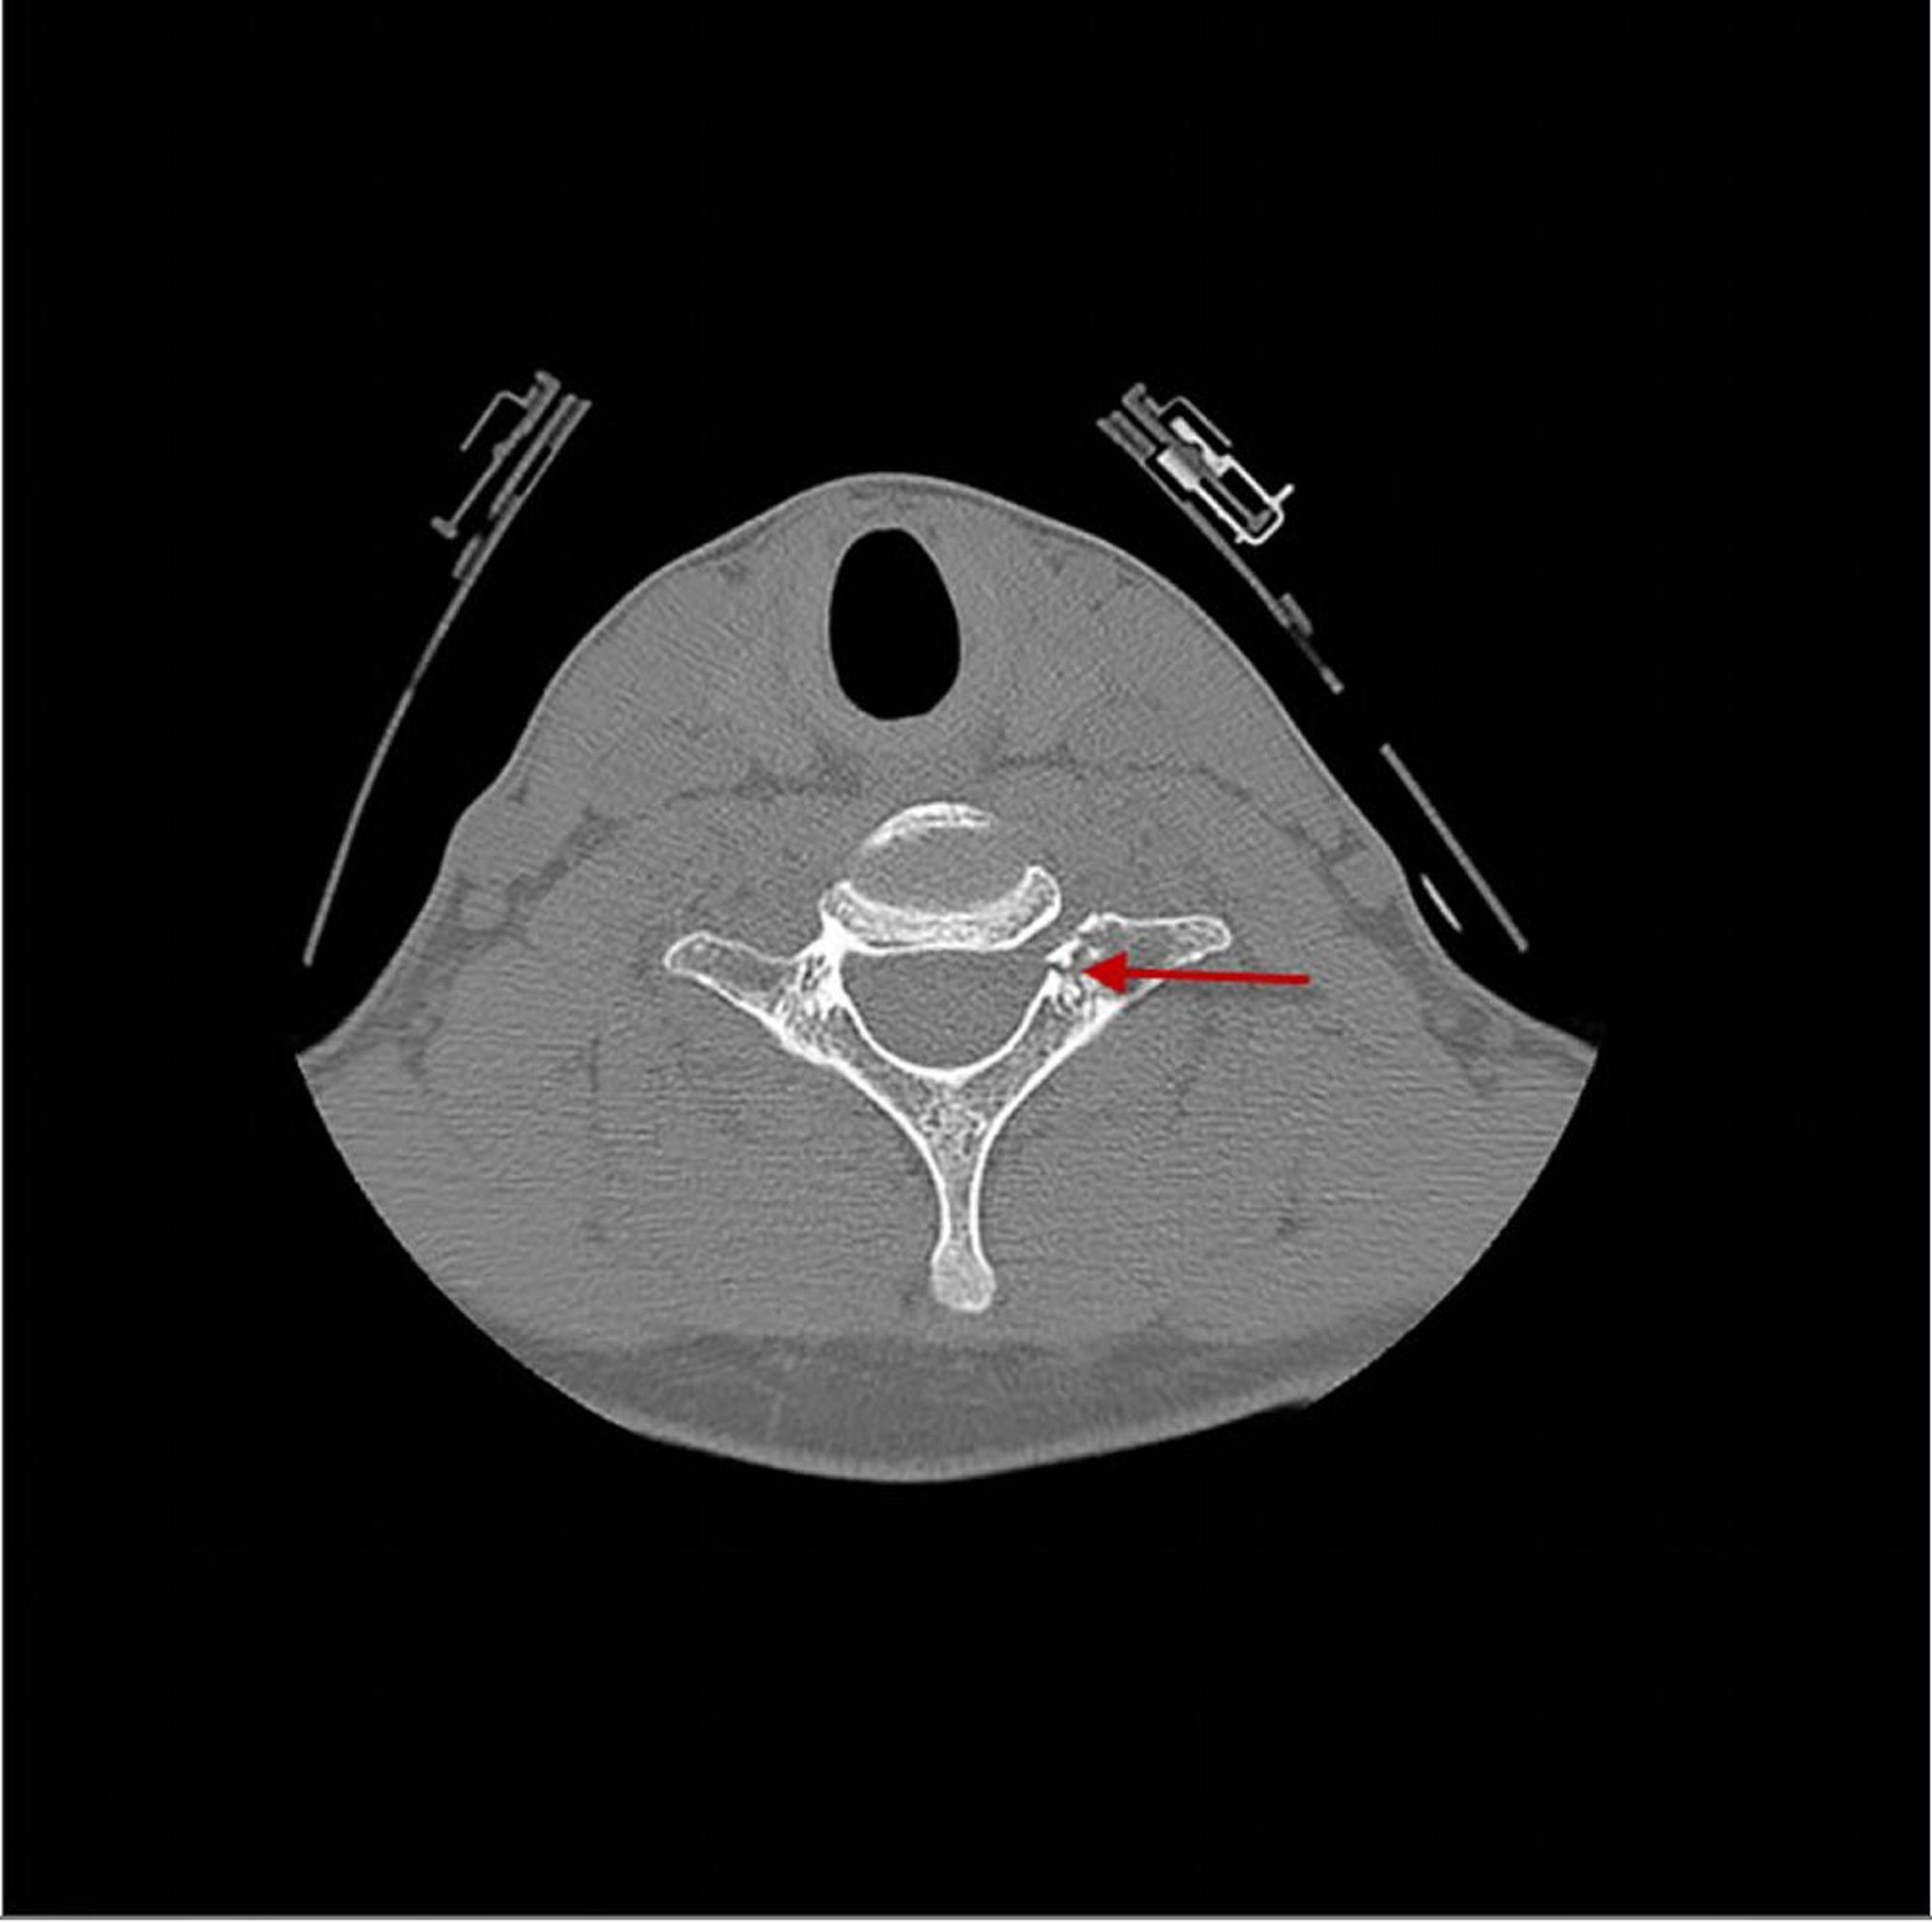

Gebrochener Halswirbel

Dieses CT zeigt eine Fraktur (Pfeil) durch den 7. Halswirbel direkt posterior des Wirbelkörpers.